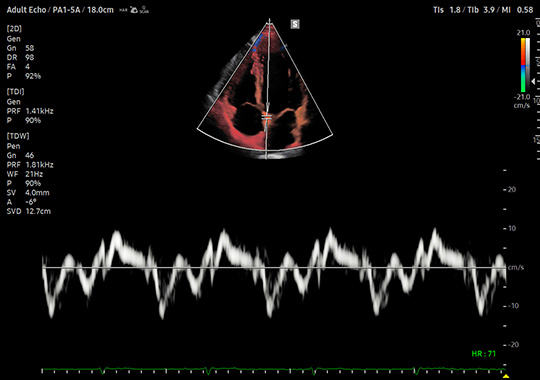

PA1-5A

- Wide Band Phased Array

- Application: Abdomen, Cardiac, Pediatric, TCD, Thoracic, Vascular